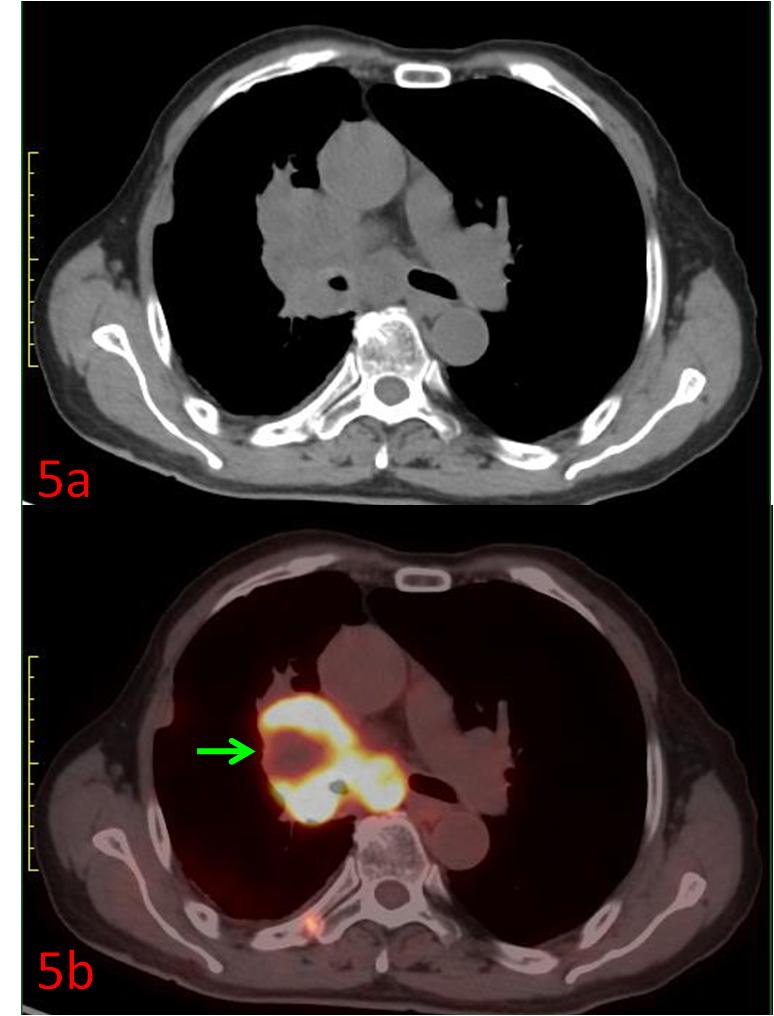

例5:中年女性,右肺上葉小細(xì)胞癌,CT示右肺門腫塊(圖5a),PET/CT展示了腫瘤內(nèi)部代謝的不均質(zhì),中心區(qū)域存在部分壞死組織(圖5b綠箭),為放療計劃制定提供更準(zhǔn)確信息。